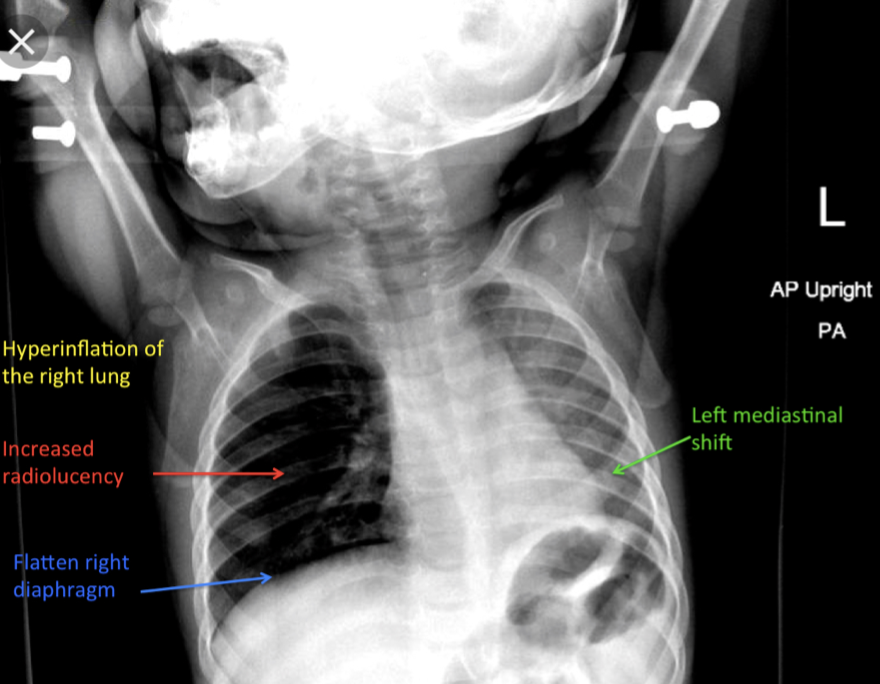

How will an inhaled foreign body appear on a CXR?